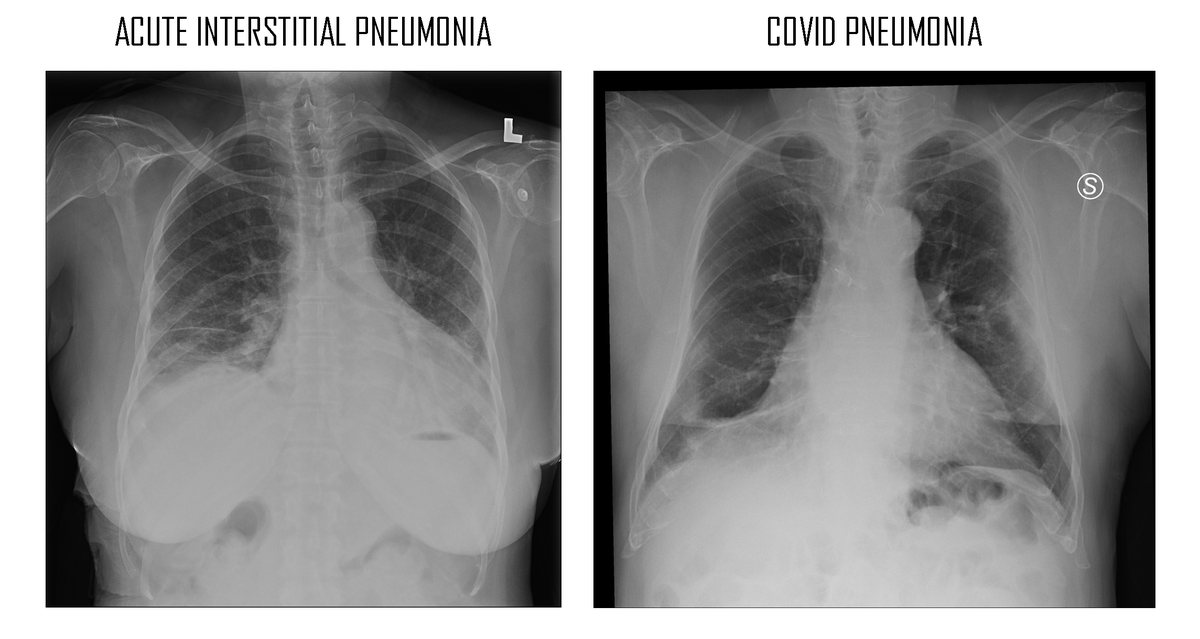

ICH GLAUBE, DASS SICH DIE COVID-PNEUMONIE IN WIRKLICHKEIT ALS EINE SEHR SELTENE KRANKHEIT TARNT: AKUTE INTERSTITIELLE LUNGENENTZÜNDUNG, VERURSACHT DURCH SPIKE-PROTEIN-IMMUNKOMPLEXE, DIE ZU FIBROSE FÜHREN

[image]

Es handelt sich um eine interstitielle Lungenentzündung. Den meisten Menschen ist jedoch nicht bewusst, dass es sich bei der interstitiellen Pneumonie um eine Seltene und sehr schwerwiegende Erkrankung handelt.

Die COVID-Pneumonie ist im Wesentlichen eine akute interstitielle Pneumonie. Die akute interstitielle Pneumonie (AIP - auch als Hamman-Rich-Syndrom bekannt) ist eine akute, rasch fortschreitende idiopathische Lungenerkrankung, die häufig zu fulminantem Atemversagen und akutem Atemnotsyndrom (ARDS) führt. Klinisch unterscheidet sie sich von anderen Formen der interstitiellen Lungenentzündung durch das rasche Auftreten von Atemversagen bei Patienten ohne vorbestehende Lungenerkrankung. Louis Hamman und Arnold Rich beschrieben sie erstmals 1935 als fulminante diffuse interstitielle Fibrose der Lunge.

Da diese COVID (AIP)-Pneumonie 9-12 Tage nach dem ersten Auftreten der Symptome auftritt (NACH der Beseitigung des Virus, also nicht DIREKT durch das Virus verursacht), kann sie als "schnelles Auftreten von Atemversagen bei einem Patienten ohne vorbestehende Lungenerkrankung" bezeichnet werden!